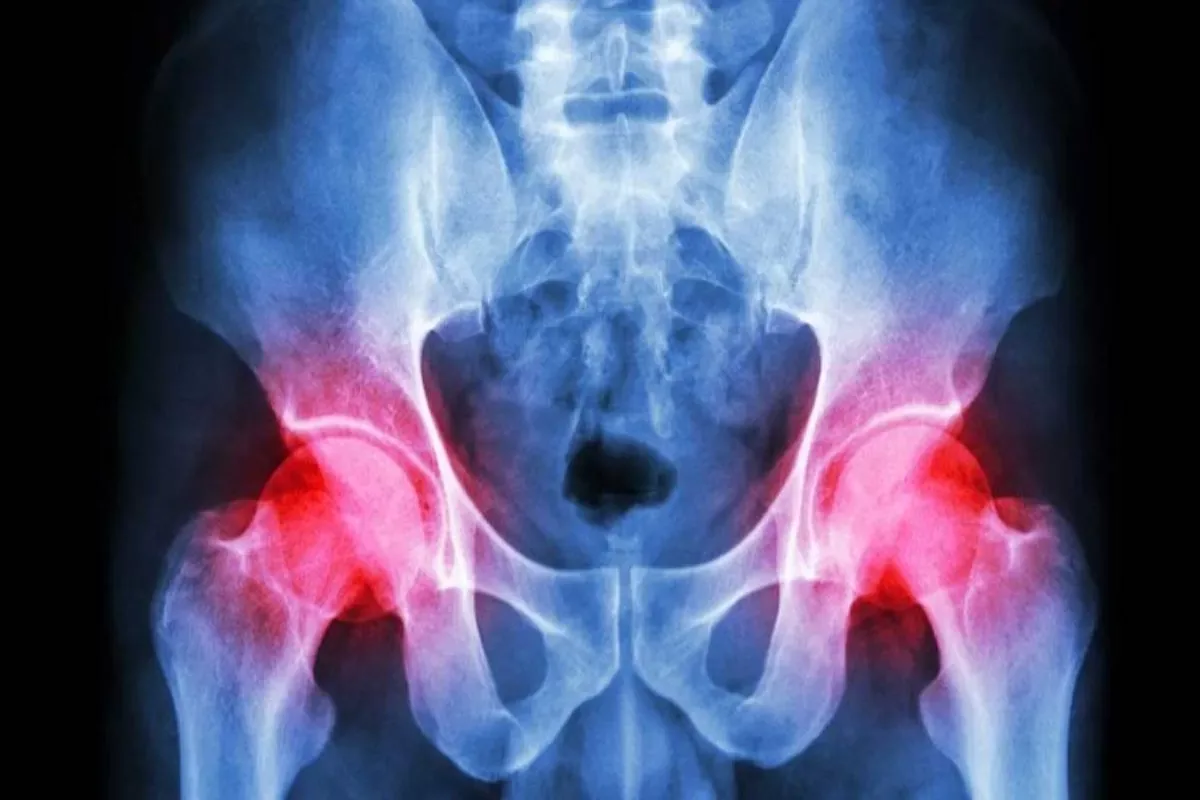

Heupklachten kunnen buitengewoon vervelend zijn en verschillende oorzaken hebben, variërend van overbelasting tot artrose of ontsteking. Deze klachten kunnen je ...